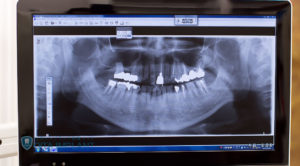

マイクロスコープを使うことにより、肉眼や拡大鏡(ルーペ)を用いた治療もマイクロスコープを使った治療と治療自体は同じものでも、肉眼では見えないぐらい小さな虫歯を発見した場合、初期段階での治療をすることが可能になり、肉眼では見られないほど暗く狭い根管部分(歯の根の部分、神経が入っている管)も、マイクロスコープを使った治療では明るく拡大できるので、従来のレントゲンを参考にしながら長年の経験と勘を頼りにしていた治療とは大きな差が出ます。虫歯治療はもちろん、特に精密さが求められる根管治療やインプラント治療などでも使用されています。

マイクロスコープを使った歯科治療は、リアルタイムでモニター画面を通じて高倍率での治療をその場で見ることができるため、患者さんご自身で確認することもできます。さらに別に口腔内カメラもあり、静止画として後で違う角度から見直すことも可能です。マイクロスコープを使用しなければ判らない程の微妙な虫歯の治療に際して、出来る限り健康な歯を削らずに患部だけを治療する精度の高い治療が可能になり、歯に優しい治療を行うことができます。また虫歯により弱くなってしまった歯は、根の先に感染を起こしやすくなります。その際、肉眼での治療が難しく精密さが求められる根管治療の場合では、マイクロスコープを使うか使わないかで処置後のトラブル発生率が大幅に変化します。さらに根の先の感染が大きく、歯根嚢胞(歯の根の先から汚れが骨の中に広がってしまい、膿の袋ができたもの)ができてしまった場合、手術が必要になることがありますが、この手術も繊細さを必要とするため、マイクロスコープは大きな役割を発揮します。